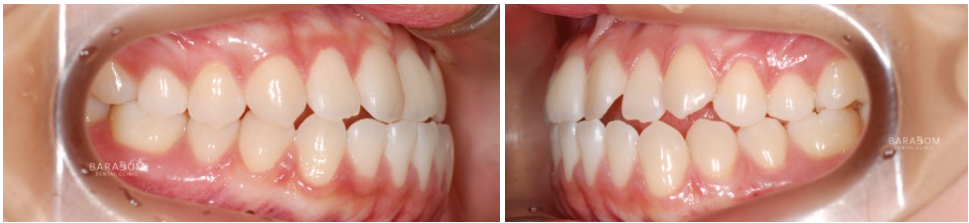

안모의 문제뿐만 아니라

부정교합도 함께 관찰됩니다.

안모와 동일하게 좌우

다른 문제를 가지고 있죠.

1️⃣좌측은 일부 치아가

거꾸로 물리는 반대교합 양상이

확인됩니다.

이런 경우 불안정한 힘이

치아에 가해져 파절로

이어질 수 있습니다.

2️⃣우측은 앞니의 끝부분 즉 절단연끼리

맞물리고 있는데요,

이를 절단 교합이라 부릅니다.

이렇게 맞물리는 양상 역시

힘을 고르게 분산시키기 어려워

절단연 파절로 이어질 수 있으며

턱관절에 안정을 찾기 어렵고

과도한 긴장 상태를 유지하게 됩니다.

윗니가 아랫니를 덮는 것이

정상적인데, 이 경우

정반대로 아래가 위를 덮는 듯한

모습이 관찰됩니다.

✅더불어 구치부의 맞물림 역시

올바르지 못한데요,

윗턱 성장 부전이 있어

골격성 3급으로 진단됩니다.

더불어 아랫턱이 좌측으로 변위되며

비대칭을 이루고 있습니다.

치료를 받은 지 17개월 가량이 지난 후 모습입니다.

1️⃣반대 및 절단 교합 양상이

모두 해소되었으며,

2️⃣골격적인 문제의 한계를 넘어

아랫턱과 윗턱이 조화를

이루는 모습이 관찰됩니다.

또한 윗니가 아랫니를 덮으며

정상적인 피개량을 가지고 있는데요,

하악 전체 치열 후방 이동과

상악 앞니의 정출을 통해

교합의 안정과 함께

심미를 되찾은 모습입니다.